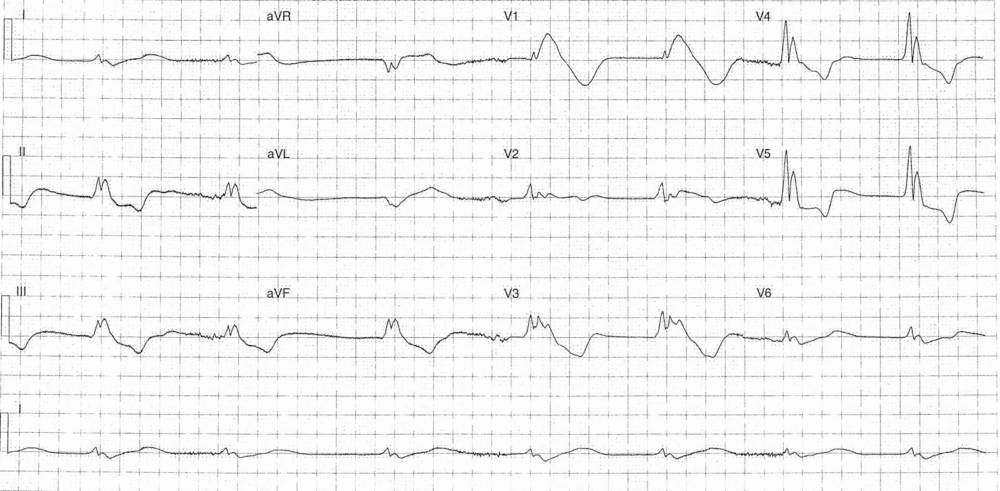

The following ECG is from a 44-year-old male with a history of non-complaint Type 1 diabetes. He has been found at home in a semi-conscious state.

ECG Case 284

What’s your interpretation ?